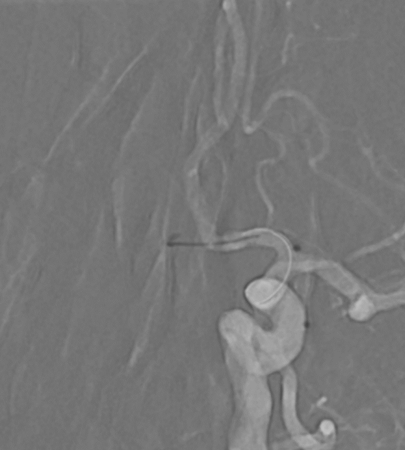

Case : AVM of leg with Pain & Limp.

Rx : AVM Embolization with Glue

#avm #embolization #irad #interventionalradiology #MedTwitter #Mumbai @ISVIRIndia @JVIRmedia @SIRspecialists @SIRRFS @cirsesociety @ApolloHosMumbai